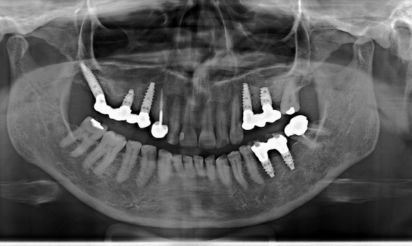

Case1 X Ray

Case2 X Ray